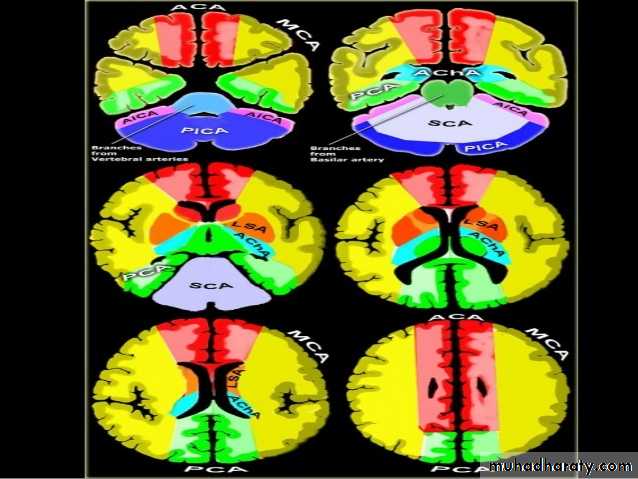

• Role of CT and MR in patients with stroke• Early CT and MR signs of infarction